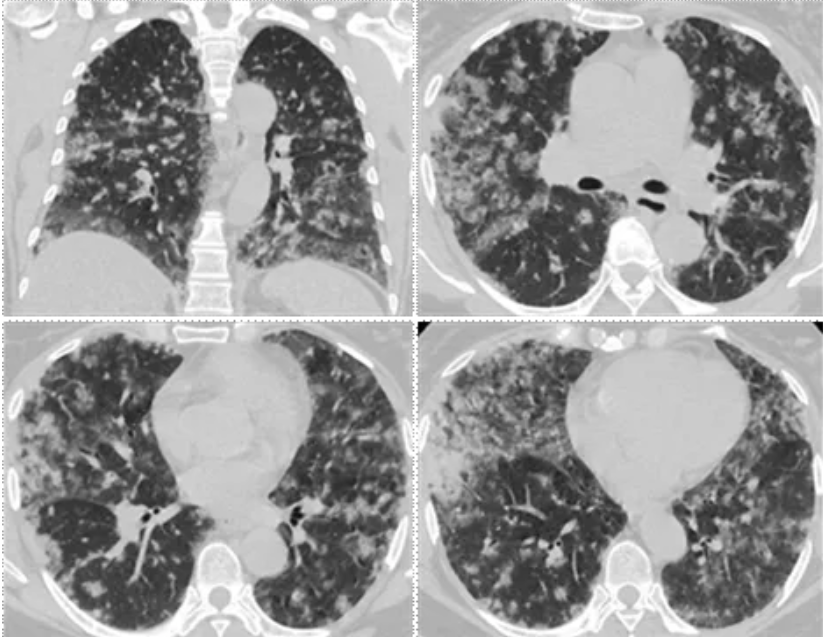

胸部 CT:双肺弥漫斑片状磨玻璃密度灶,部分边界欠清,病变主要沿支气管血管束分布,以双肺中外带、胸膜下为著,其内可见小叶间隔增厚,伴多发片状小实变灶(图1)。

图1.